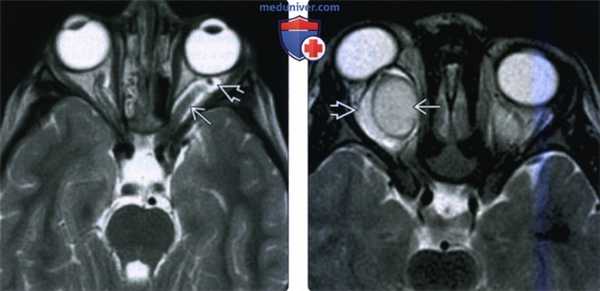

(Слева) На рисунке на аксиальном срезе показана глиома левого зрительного нерва, распространяющаяся по его внутриглазничной части через расширенный канал зрительного нерва в пре-хиазмальный сегмент. Показана характерная веретеновидная форма расширения зрительного нерва.

(Справа) При МРТ Т2ВИ FS в аксиальной проекции определяется веретеновидное утолщение и аномальный изгиб внутриглазничной части левого зрительного нерва, вызывающее небольшой экзофтальм. На Т2ВИ опухоль гиперинтенсивна, что характерно для глиомы зрительного пути. Обратите внимание на неизмененную периневральную жидкость позади опухоли. (Слева) При кососагиттальной МРТ Т1ВИ FS с КУ определяются глобулярное утолщение и интенсивное гомогенное контрастирование внутриглазничного отрезка зрительного нерва, тянущиеся в заднем направлении в расширенный канал зрительного нерва.

(Слева) При МРТ Т2ВИ в аксиальной проекции определяется аномальное утолщение внутриглазничного сегмента левого зрительного нерва. Влагалище зрительною нерва кпереди от опухоли расширено и изогнутой.

(Справа) При МРТ Т2ВИ в аксиальной проекции отмечаются расширение и умеренная Т2 гиперинтенсивность внутриглазничного сегмента правою зрительною нерва. Периферическая зона повышенной интенсивности сигнала отражает сопутствующую гиперплазию паутинной оболочки.